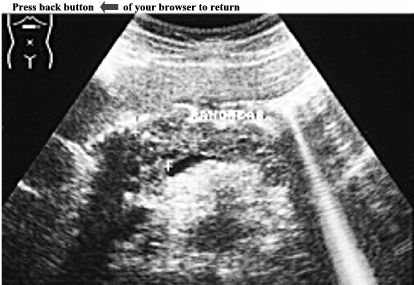

CASE 4:

Transverse examination of epigastric region shows a normal sized pancreas with irregular contours. Pancreatic parenchyma is non-homogeneous. Small hyperechoic multiple foci with acoustic shadowing are visible mainly in the head of the pancreas. Anechoic structures, scattered all over pancreas correspond to ductal dilatation.

ANSWER:

Chronic pancreatitis